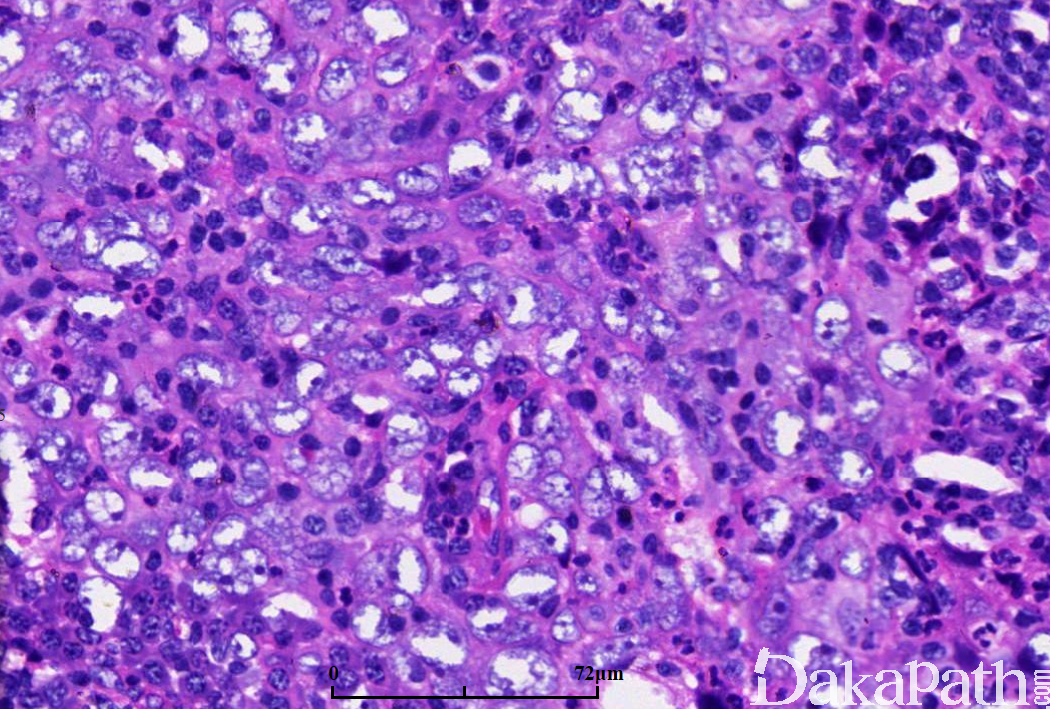

未分化型鼻咽癌

癌细胞呈片块状,核空泡状,核膜光滑,核仁大、嗜伊红;

间质中淋巴细胞丰富,嗜酸粒细胞、浆细胞、上皮样细胞及多核巨细胞均多见;

坏死易见。